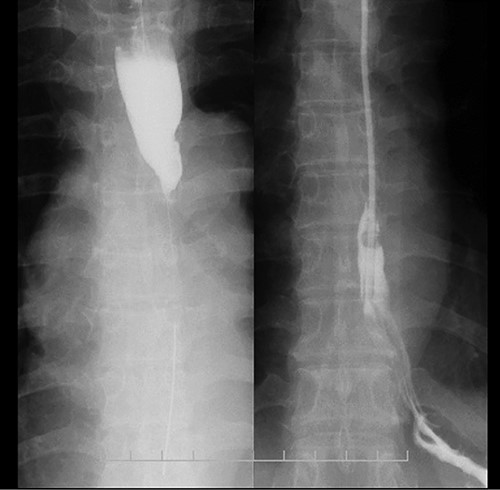

CT images showing a horizontal section of the esophagus; CT image shows circumferential wall thickening with infiltrative changes in the middle part of the thoracic esophagus.

Preoperative computed tomography (CT) and barium meal studies were performed. The CT findings showed circumferential wall thickening with infiltrative change at the middle of the intrathoracic esophagus, with luminal dilation of the oral side of the stenotic esophagus (Figs 2, 3). The barium meal study showed no abnormal findings in the stomach (Fig. 4). Thoracoscopic esophagectomy was performed with the patient in the semi-prone position, followed by esophageal reconstruction using a gastric tube with the patient in the supine position. The operation was started with bilateral lung ventilation using a single-lumen endotracheal tube. A four-port thoracoscopic technique was used as follows: an observation port with a 10-mm scope was placed at the ninth intercostal space at the line of the inferior scapular angle, and two 5-mm ports and one 12-mm port for the intrathoracic procedures were placed at the third, fifth and seventh intercostal spaces, respectively, at the posterior axillary line (Fig. 5). Pneumothorax was created using 10 mmHg of CO2 to deflate the lung to achieve a better operative field. The pleura and connective tissue around the thoracic esophagus showed severe inflammatory and fibrotic changes. In particular, the middle thoracic esophagus was strongly adherent to the arch of the azygos vein and the tracheal bifurcation.